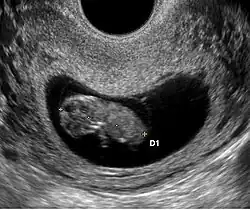

L'aspect échographique du tout début de grossesse

• Le premier signe échographique d'une grossesse est la visualisation d'un sac ovulaire. Il est visible entre 4 semaines et 1 jour et 4 semaines et 3 jours; Il mesure alors 2 à mm. L'utilisation de la voie endovaginale est souvent nécessaire pour le voir. Le sac ovulaire a l'aspect d'une petite tache noire, excentrée par rapport à la cavité utérine, correspondant à la cavité chorionique entourée d'une couronne d'échogénéicité forte : le trophoblaste.

• À cinq semaines, le sac ovulaire mesure mm. Il est quasiment toujours visible lors de l'échographie par voie abdominale. Il est parfois difficile d'affirmer la localisation intra-utérine de la grossesse en raison de l'aspect de pseudo-sac gestationnel décrit au cours des grossesses extra-utérines. Seuls deux signes sont pathognomoniques de la grossesse intra-utérine

• L'aspect en double cercle du sac (double decidual sac sign) correspondant une couronne hyper-échogène interne en rapport avec la trophoblaste et une couronne hypo-échogène externe en rapport avec la transformation gravidique de l'endomètre

• La visualisation de la vésicule vitelline qui affirme définitivement le caractère ovulaire de l'image échographique.

• La visualisation de la vésicule vitelline est un élément essentiel pour affirmer le caractère ovulaire de l'image et l'évolutivité de la grossesse. Embryologiquement, la vésicule vitelline visualisée correspond à la seconde vésicule vitelline. La vésicule vitelline est toujours visible à 5 semaines et 5 jours par voie endovaginale. Le sac ovulaire mesure en moyenne mm. Par voie abdominale, elle est toujours visible à 7 semaines (le sac ovulaire mesure en moyenne 20 mm). Le diamètre de la vésicule vitelline augmente de 5 à 10 semaines pour atteindre 5 à mm.